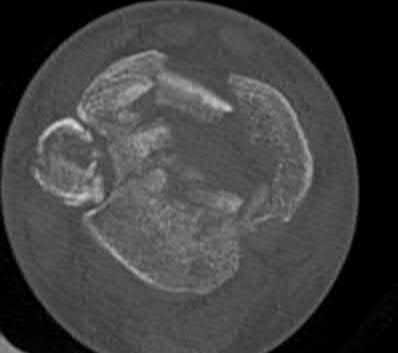

Question 20:

A 3-year-old girl is evaluated for severe, progressive bilateral genu varum. Radiographs demonstrate medial metaphyseal beaking, fragmentation, and depression of the proximal medial tibial physis. According to the Langenskiöld classification of infantile Blount's disease, at which stage does an overt physeal bony bar (epiphyseal-metaphyseal bridge) definitively form across the medial physis, conferring a high risk of recurrence without bar excision?

Correct Answer: Stage VI

The Langenskiöld classification describes progressive radiographic changes in infantile Blount disease. Stage I-IV show worsening metaphyseal beaking and stepping. Stage V shows a deep cleft separating the medial epiphysis into two portions. Stage VI is definitively characterized by the formation of a solid medial physeal bridge (bony bar) between the epiphysis and metaphysis, halting medial growth completely and often requiring bar resection along with osteotomy.